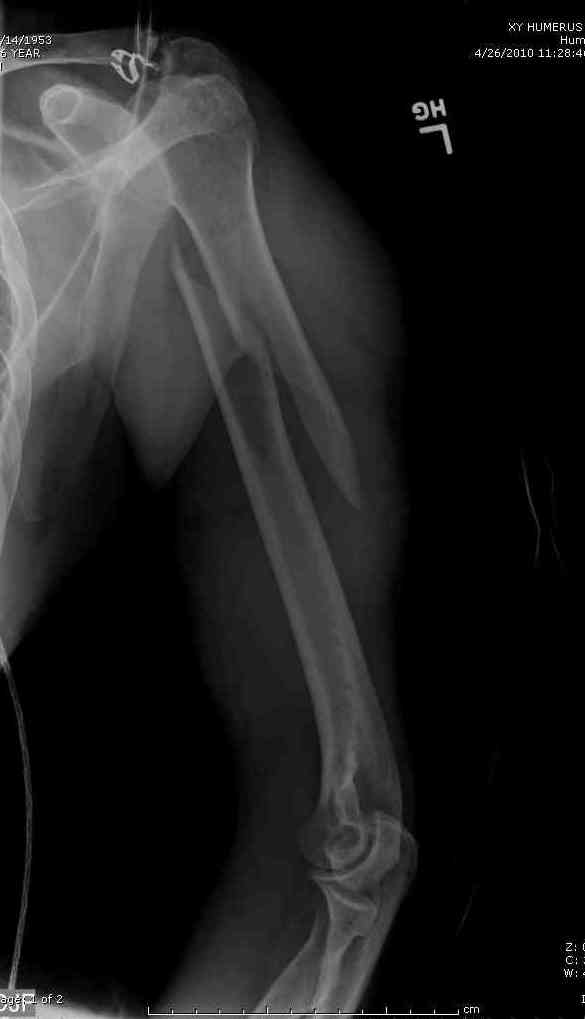

Александр А. 01 Июль 2010, 00:29

Добрый вечер!

Приложение как пример.

Спасибо.

Консервативно он уже лечился до этой операции в течение трёх с половиной месяцев.

А именно такой вариант операции выбран из экономических соображений.

вообще, торчашие в субакромиальное пространство шипы оставляют неизгладимое впечатление. Не думаю, что таким имплантом есть смысл гордиться